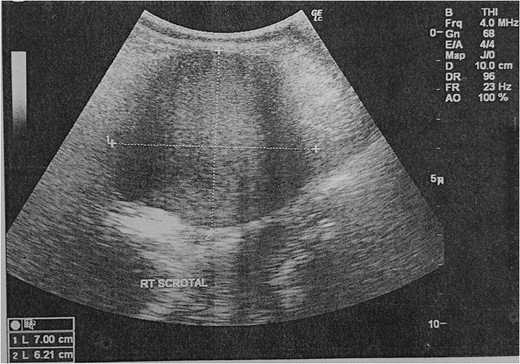

We proceeded with an ultra-sonographic examination of the scrotum, which revealed a heterogeneous mass within the right scrotal sac measuring 7.0 cm × 6.2 cm. The normal right testicle was not seen (Fig. 1). The features were pointing towards a right testicular tumour. Thus, a computed tomographic (CT) scan was ordered, which revealed a right inguinal hernia containing greater omentum and a heterogeneous mass suggestive of a right testicular tumour as seen on the ultrasonography (Figs 2 and 3).

Ultrasonography of the scrotum showing a heterogeneous mass within the right scrotal sac.